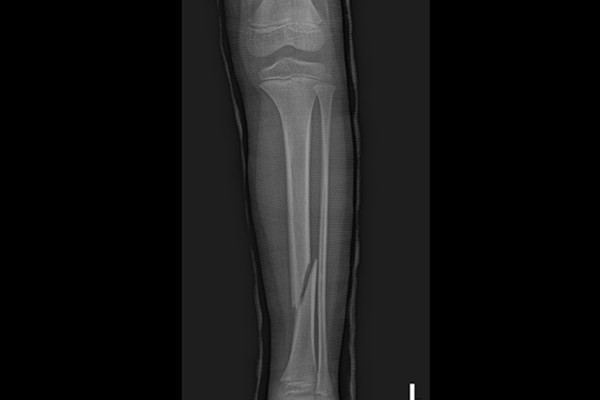

강원도 철원군에 거주중이신 8세 남자아이 환자분께서 좌측 정강이뼈 골절로 내원해주셨습니다. 약 1주일 전 시소에서 떨어지며 다치셨고, 타병원에서 통깁스를 통한 보존적 치료를 시행중이었으나, 뼈가 어긋나 수술적 치료가 필요하다는 소견을 듣고서 보호자분께서 검색을 하여 골절수술을 많이 하고, 족부전공자가 있는 저희 병원을 찾아오시게 되었다고 말씀하셨습니다.

내원 당시 X-RAY를 보면 정강이뼈가 부러져서 각변형(각도 변형)되어 정렬이 흐트러진 것이 확인됩니다.

측면에서 확인해봐도 골절로 인해 정강이뼈가 어긋나있음이 확인되어 소아 정강이뼈 골절(Fx. distal tibia shaft lowerleg Lt.)을 진단하였습니다.